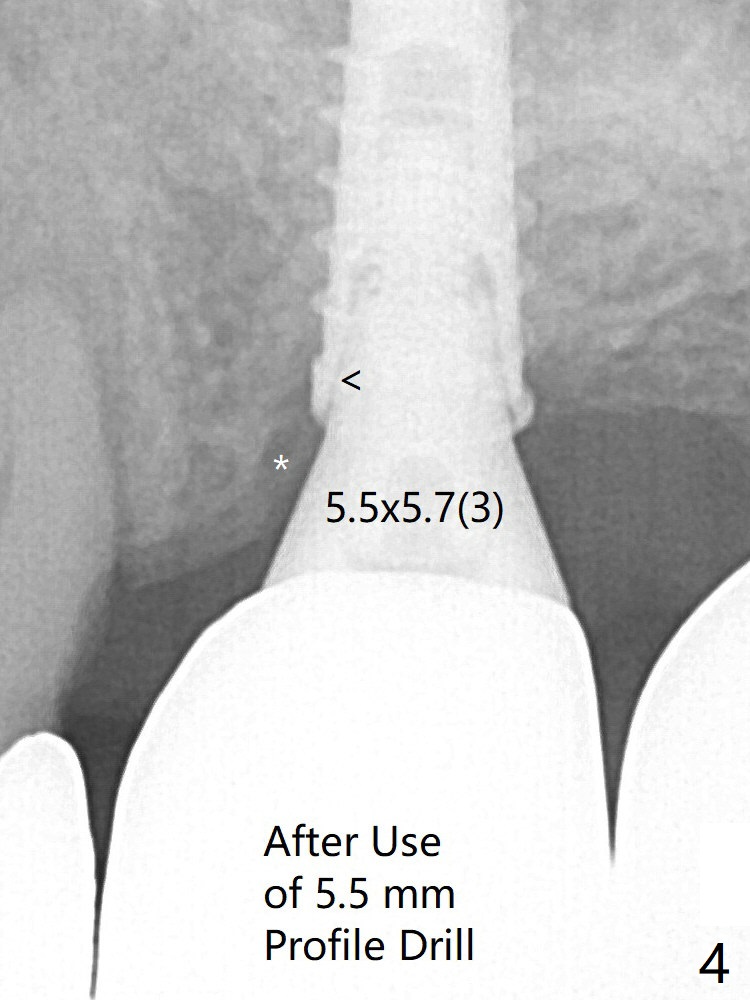

The crown/abutment at #14 is loose 1 year 10 months post cementation. After use of 5.5 mm profile drill, the crown/abutment is reseated, but the seating is incomplete (Fig.4 <) because of contact of the abutment with the mesial crest (*). A larger profile drill does not help (Fig.5). When a narrower abutment (4.5x7.5(3) mm) is torqued, it appears to be completely seated (Fig.6). After distal surface adjustment of the abutment, impression is re-taken. Depth Control Last Next Xin Wei, DDS, PhD, MS 1st edition 01/14/2020, last revision 01/14/2020